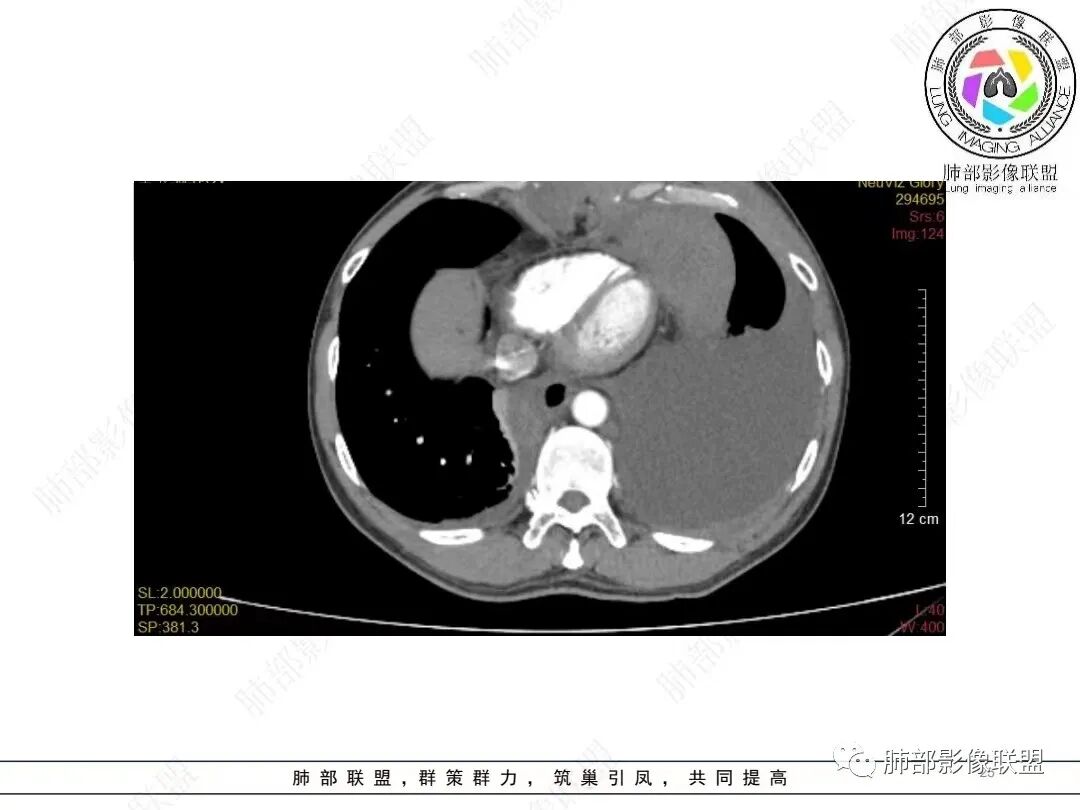

2.影像学特点:病变范围相当广泛,多发块状影累及纵隔、胸膜、前胸壁(胸大肌下)、前上腹壁等。胸膜弥漫性斑状增厚为主,明显强化,纵隔旁椭圆形块影较密实,沿胸膜分布趋势,未见支气管等结构进入。后纵隔块影较大,占位效应明显,肺静脉受累狭窄。双侧胸腔积液。

甲状腺右叶相对低密度结节影,边界清楚,不均匀分隔样强化,经验上分析与胸部病灶缺乏关联性。

肿瘤侵犯可以出现胸腔积液,静脉回流障碍也可以,如心功能不全,如本例肺静脉及左心房受压等等。

恶性肿瘤广泛侵犯转移有时反而给病灶起源的判断带来困惑。本例亦应当结合病史及其他检查排除转移瘤。